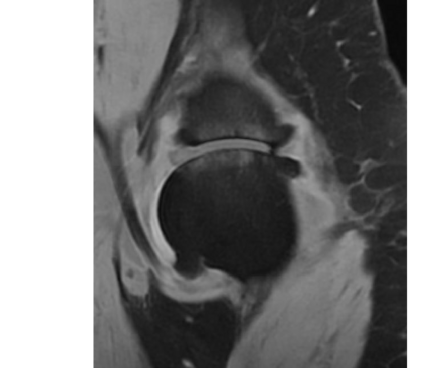

Magnetic resonance (MR) images are often acquired in 2D settings for real clinical applications. The 3D volumes reconstructed by stacking multiple 2D slices have large inter-slice spacing, resulting in lower inter-slice resolution than intra-slice resolution. Super-resolution is a powerful tool to reduce the inter-slice spacing of 3D images to facilitate subsequent visualization and computation tasks. However, most existing works train the super-resolution network at a fixed ratio, which is inconvenient in clinical scenes due to the heterogeneous parameters in MR scanning. In this paper, we propose a single super-resolution network to reduce the inter-slice spacing of MR images at an arbitrarily adjustable ratio. Specifically, we view the input image as a continuous implicit function of coordinates. The intermediate slices of different spacing ratios could be constructed according to the implicit representation up-sampled in the continuous domain. We particularly propose a novel local-aware spatial attention mechanism and long-range residual learning to boost the quality of the output image. The experimental results demonstrate the superiority of our proposed method, even compared to the models trained at a fixed ratio.